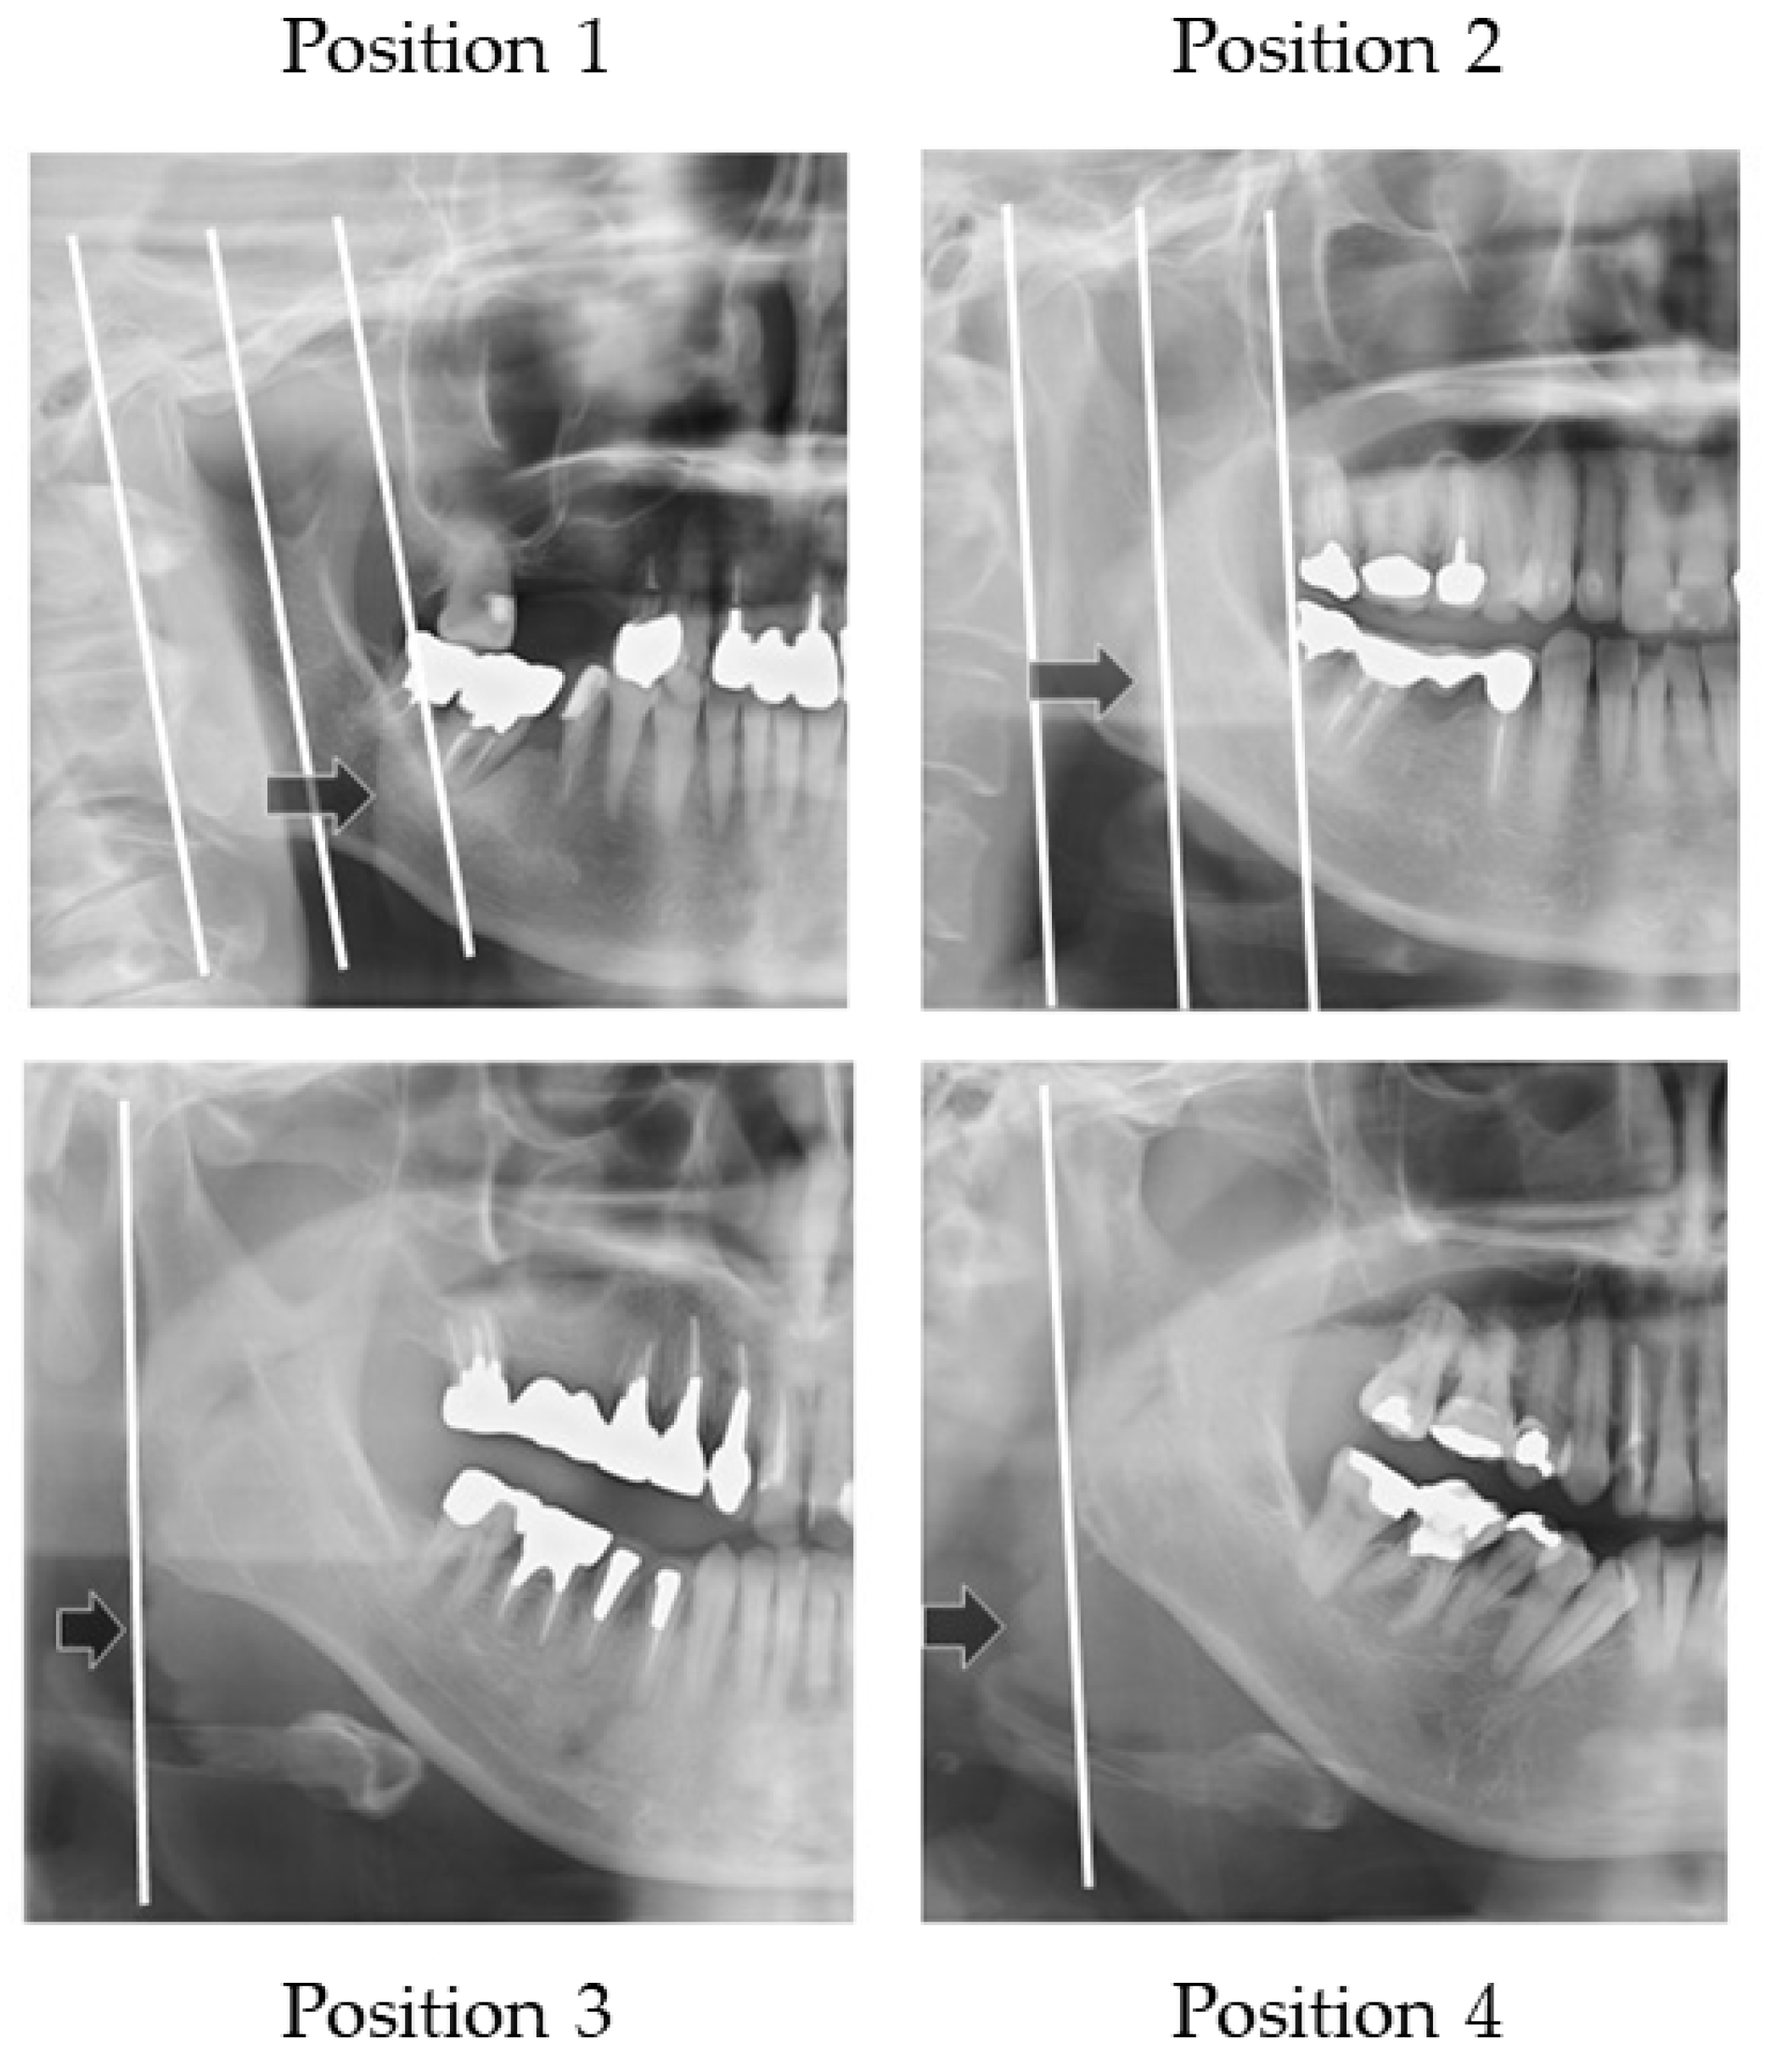

Figure 6 illustrates how to evaluate the outer position of tongue and Figure 7 shows sample images. The width of tongue was assessed according to the location where the outer border of tongue overlapped the anatomical structure. If the right side and left side of the outer border of the tongue were different, the inner position side was used.

Width of the tongue. The location where the outer border of tongue overlapped the anatomical structure was assessed.

Sample images of width of tongue. Arrows show the outer border of the tongue.

Three landmarks were defined, as follows:

- The distal border of the mandible line is a simulated line, which is defined between the posterior point of the mandibular condyle and posterior point of the angle of the mandible.

- The mesial border of the mandible line is defined as the line that is the distal border line moved in parallel to the coronoid process.

- The midline of the border of the mandible line is defined as the midline of the distal border of the mandible line and the mesial border of the mandible line.

The outer border of tongue is defined according to the following positions:

Position 1: Observed between the mesial border of the mandible line and the midline border of the mandible line;

Position 2: Observed between the midline of border of the mandible line and the distal border of the mandible line;

Position 3: Observed on the distal border of the mandible line;

Position 4: Observed outside of the distal border of the mandible line.